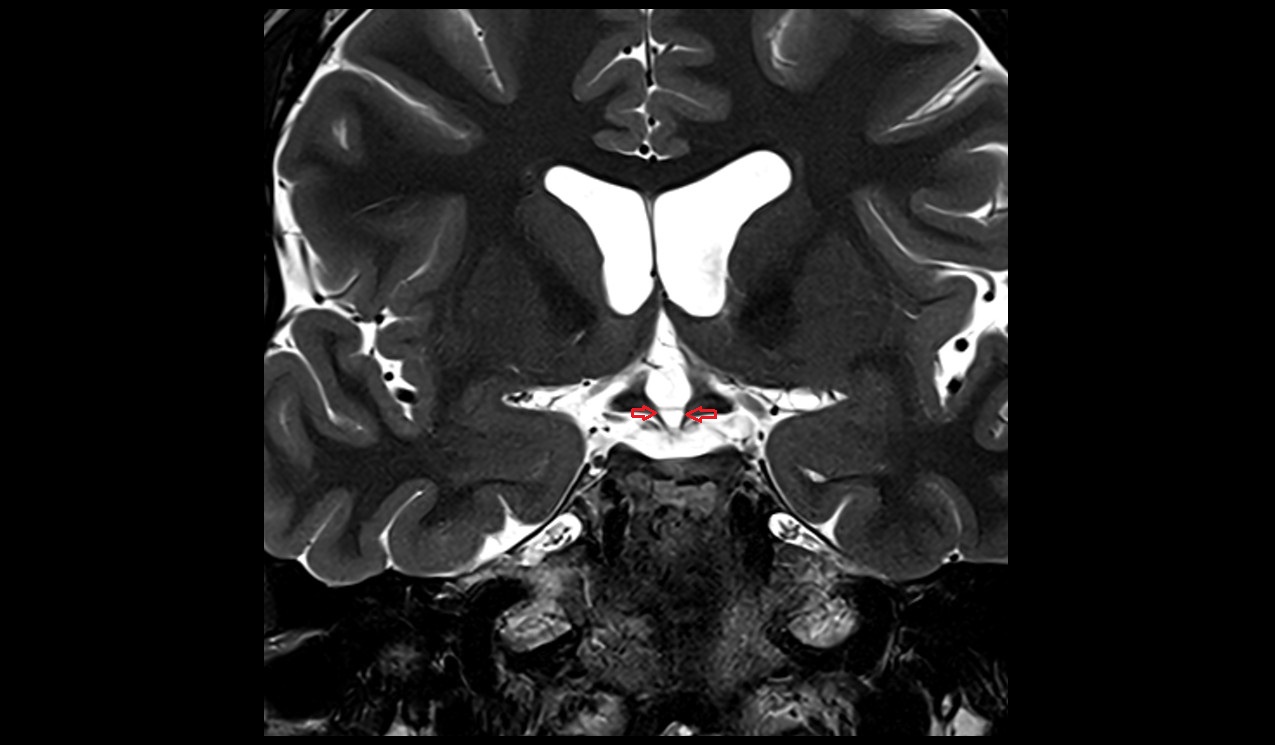

- Pituitary stalk

- Pituitary gland

- Anterior lobe of pituitary gland

- Posterior lobe pituitary gland